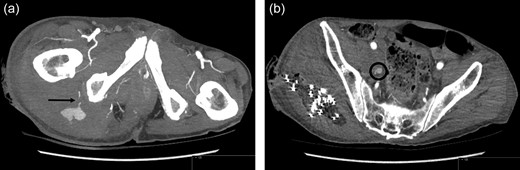

The patient continued to be haemodynamically stable throughout Thursday (day 7), abdomen and pelvis contrast CT indicated two bleeding sites arising from the internal iliac artery region. One was identified arising from the posterior division of the right internal iliac artery, at the inferior gluteal artery (Fig. 1a). A second, less prominent bleeding point was noted at the division level of the internal iliac artery into its anterior and posterior branches, anterior to the sacroiliac joint (Fig. 1b). Selective angiography was also performed, identifying a large pseudoaneurysm arising from the inferior gluteal artery and endovascular repair was undertaken (Fig. 2). The right common iliac artery was accessed via a left common femoral artery puncture and a combination of five 2 × 5.0 mm Figure 8–18 pushable coils and two VortX™-18 pushable coils of 3 × 2.5 mm and 4 × 4.0 mm respectively (Boston Scientific, Massachusetts, USA) were deployed to embolize the inflow and outflow vessels (Fig. 2). A further 200 mls of blood were evacuated from the right buttock wound post-embolization. Haemostasis was achieved successfully and wound closure undertaken on the following Monday (day 11).

Contrast CT Scan: (a) Inferior gluteal artery haemorrhage. (b) Second site of haemorrhage at the level of division of the internal iliac artery into its anterior and posterior branches, anterior to the sacroiliac joint.